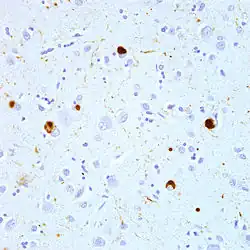

| Microscopic image of a Lewy body (adjacent to arrowhead) in a neuron of the substantia nigra; scale bar=20 microns (0.02 mm) | |